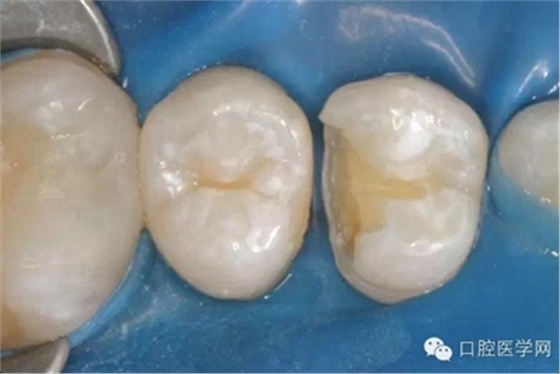

在根管治療之前我們要做麻醉,所以整個(gè)治療的過(guò)程是不疼的。治療過(guò)程中要使用橡皮障,只露出要治療的牙齒,口腔其他部分都在橡皮障之下,可以隔開(kāi)唾液,因?yàn)橥僖豪镆彩怯屑?xì)菌的,如果一邊清理,一遍有唾液流到根管內(nèi)部,那么就無(wú)法做到完全無(wú)菌。同時(shí),有橡皮障的隔絕作用,可以防止治療器械掉到嗓子里,這一點(diǎn)非常重要。